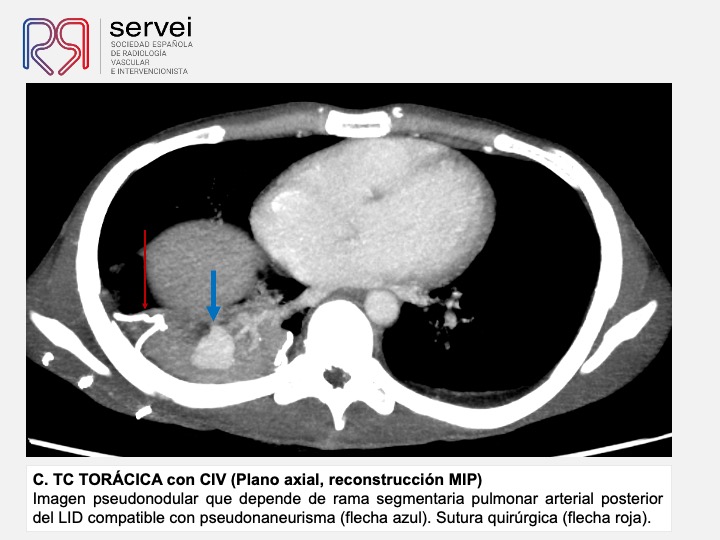

Pseudoaneurisma pulmonar secundario a herida por arma de fuego